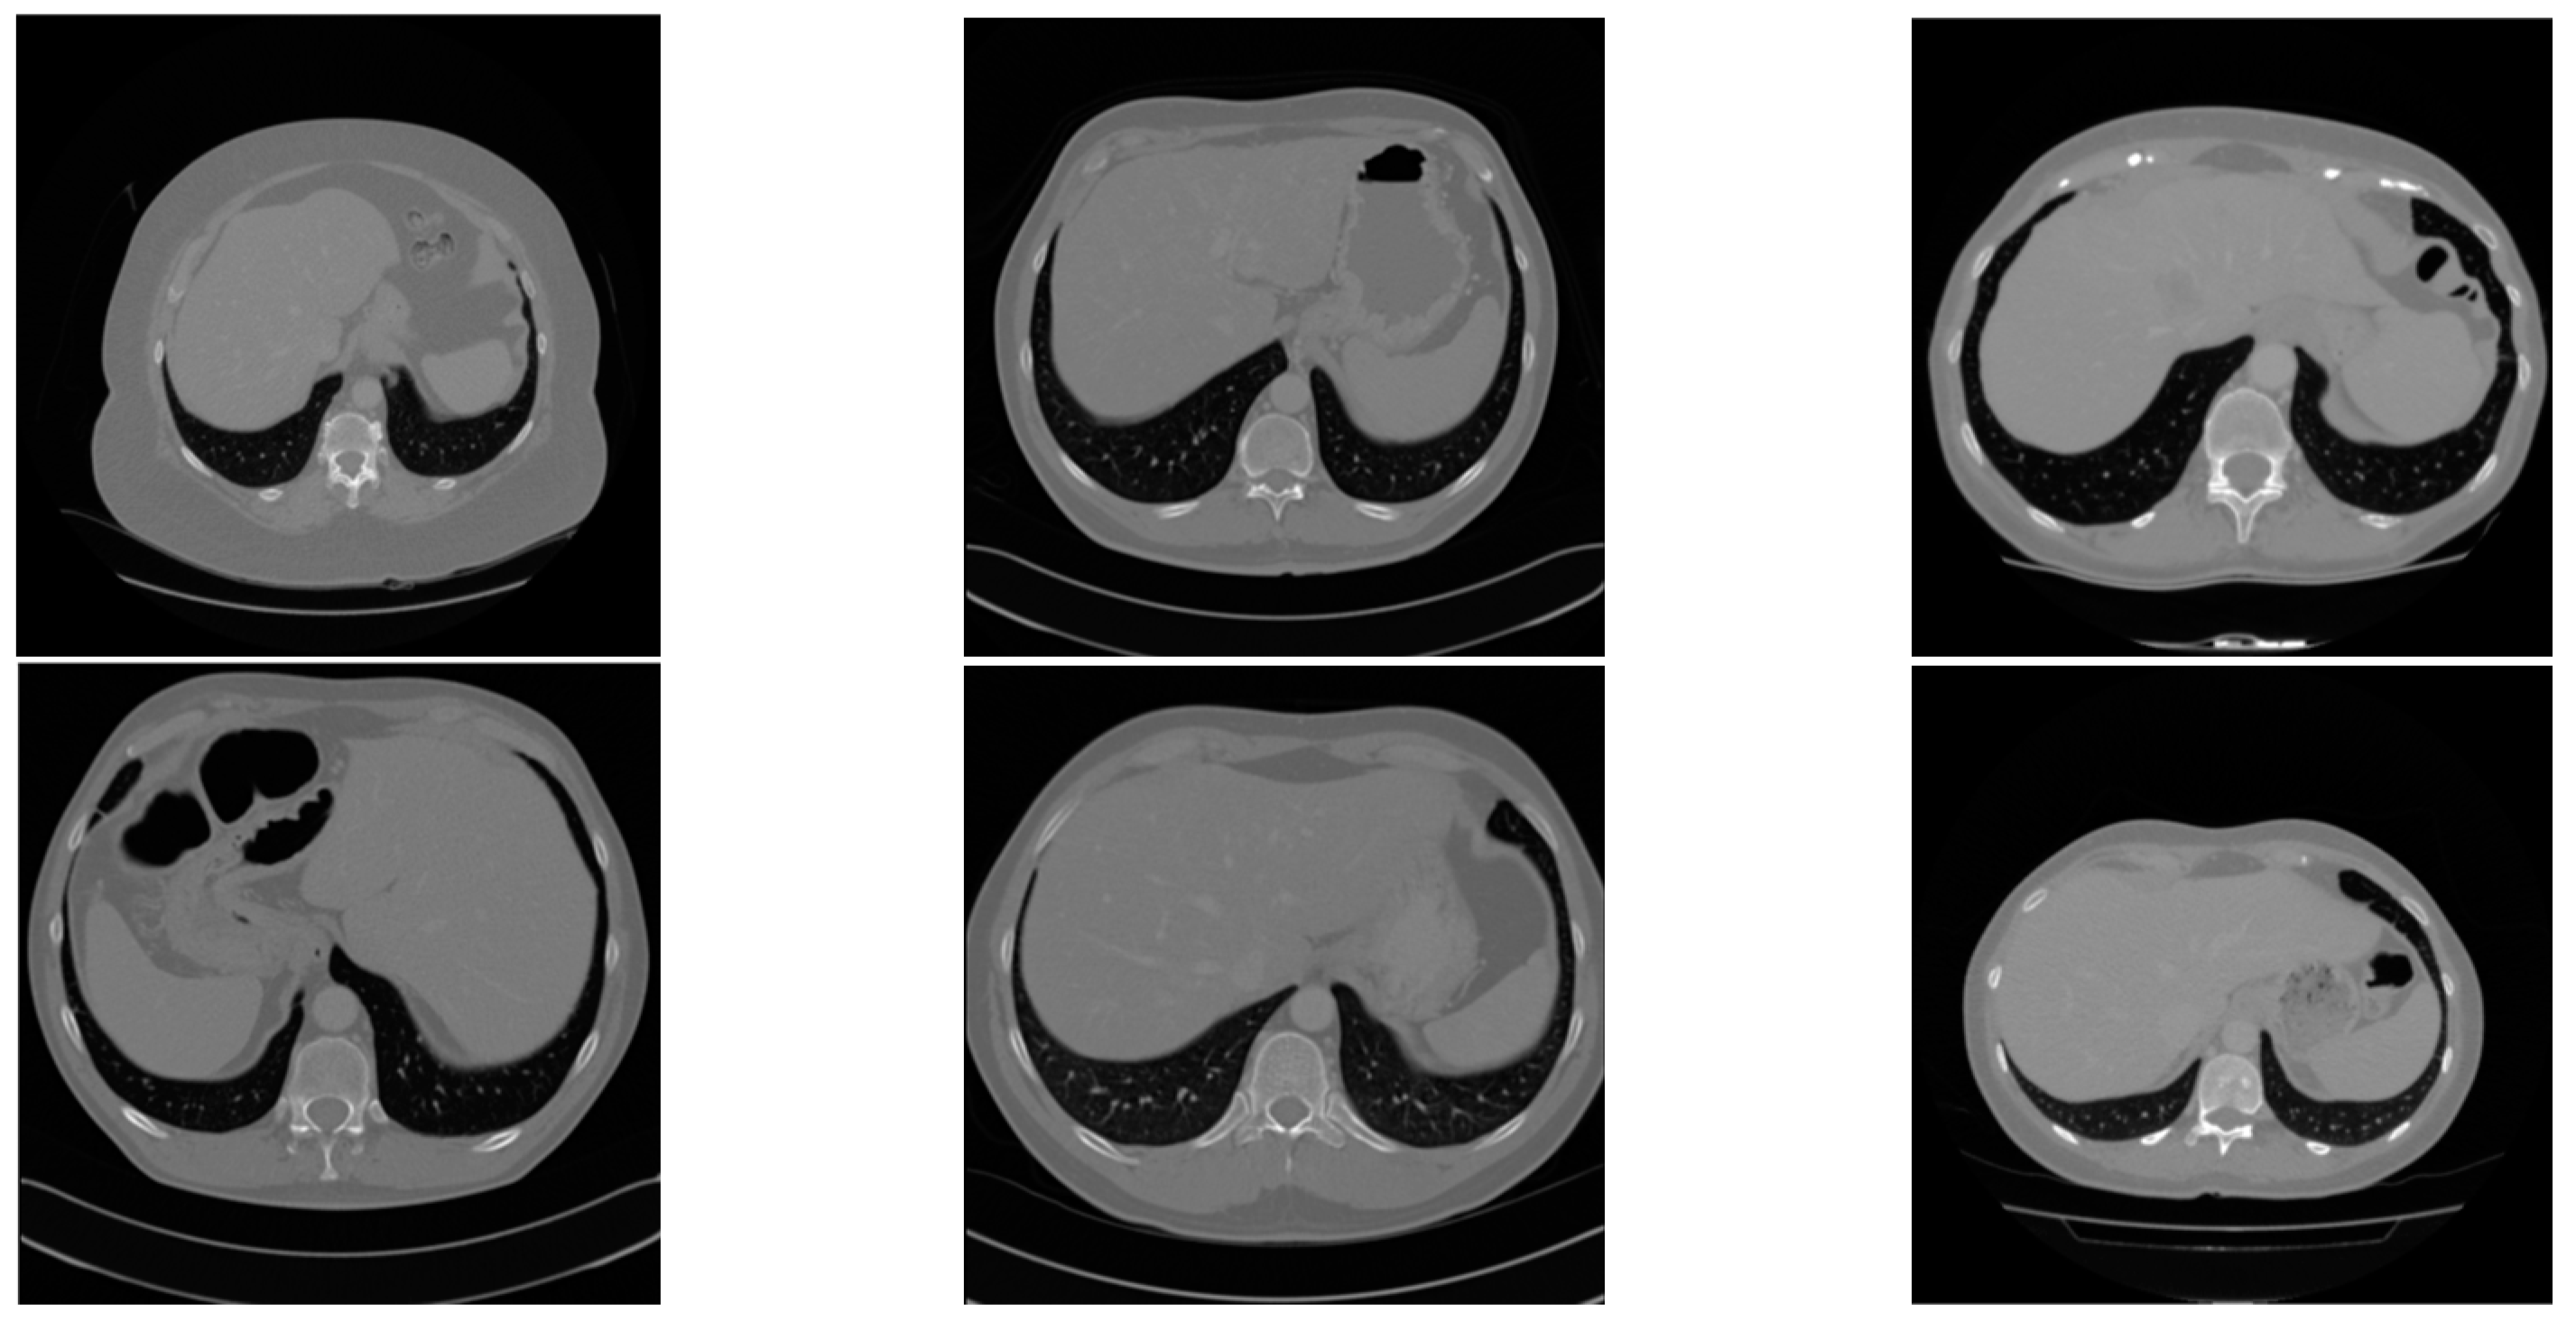

4.1. Datasets

4.2. Data Preprocessing and Augmentation